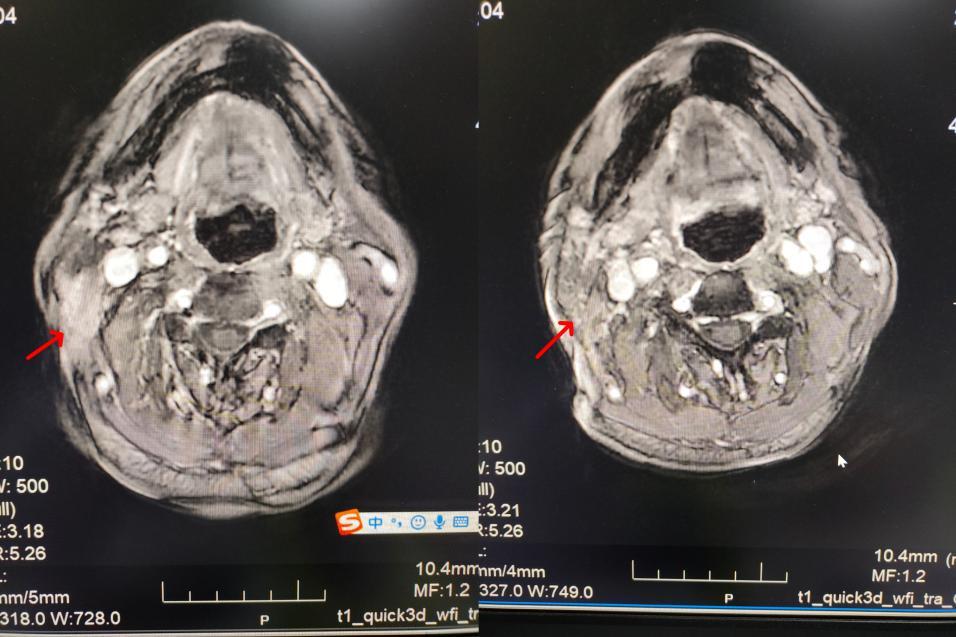

接诊后,肿瘤二科主任曹苏娟带领团队对张爷爷的病情进行了全面评估。“患者颈部的肿块紧邻咽喉部位,若采用传统放疗,极易损伤咽喉黏膜与唾液腺,进而引发咽喉疼痛、吞咽困难等不良反应,不仅会影响正常进食,导致生活质量大幅下降,还可能让患者无法耐受完整疗程。” 曹苏娟主任一语道破治疗难点。

针对张爷爷的特殊病情、年龄等因素,科室医护团队迅速展开研讨,为其量身定制了TOMO放疗的个性化治疗方案。与传统放疗相比,TOMO放疗犹如为射线配备了“精准导航”,能够对肿瘤病灶实施精准靶向“打击”,同时最大限度保护周边的唾液腺、咽喉黏膜等正常组织,显著提升了患者的治疗耐受性。